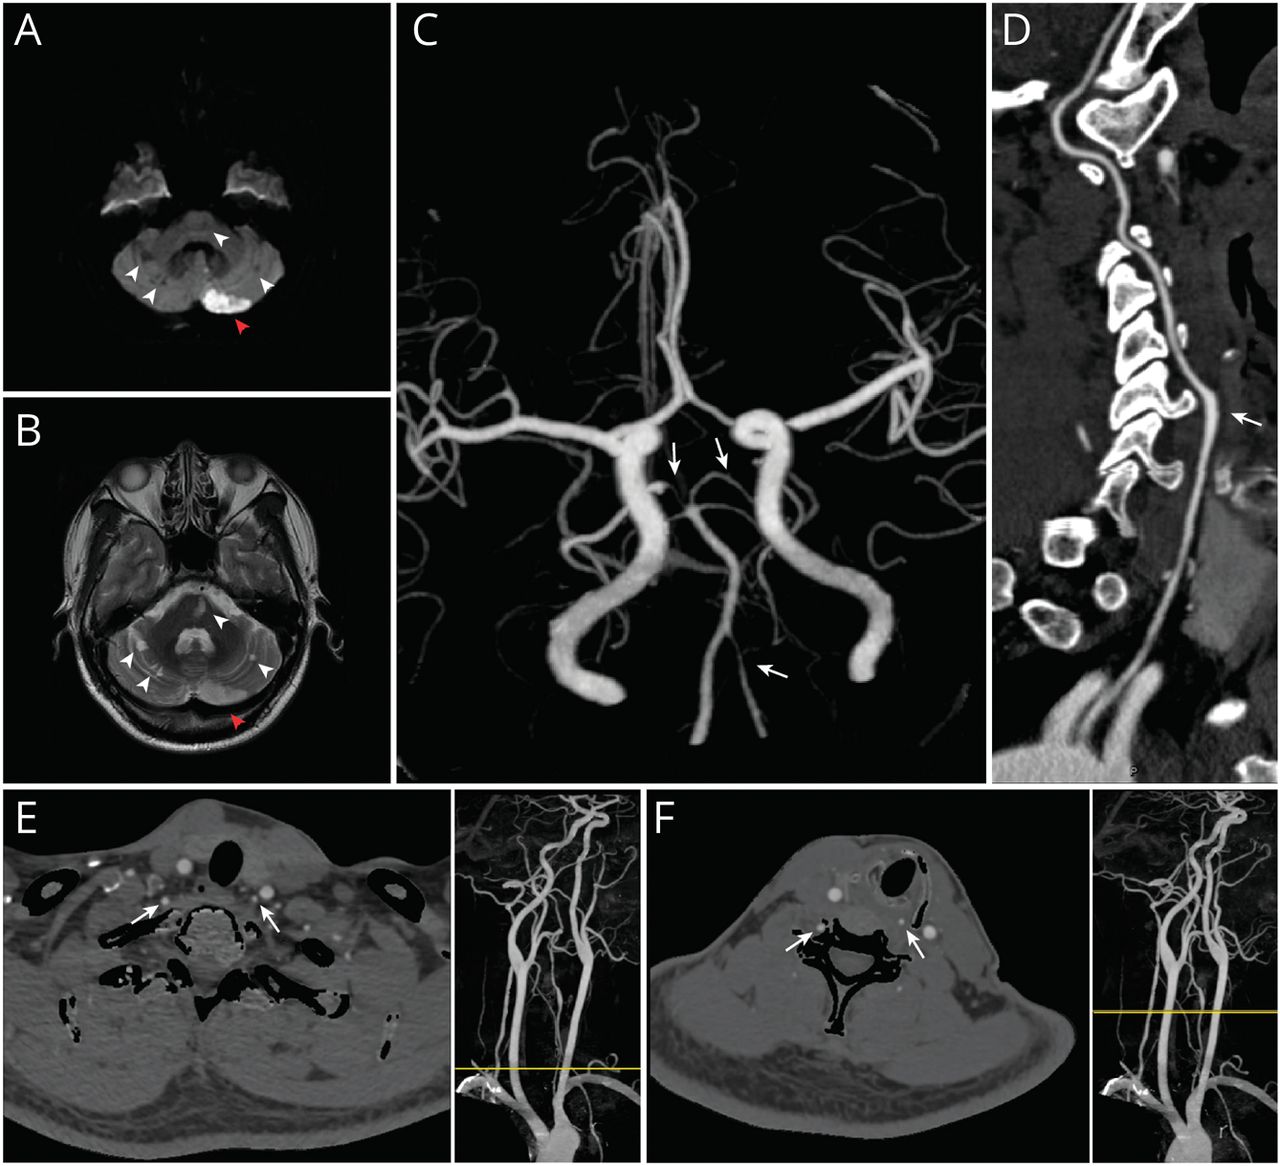

• A Comprehensive Diagnostic Workup In the neutral head position (A), SPECT demonstrates adequate blood flow in the left cerebellar hemisphere (B, dashed frame); TCD displays a normal spectrum with blunt peaks and gentle slopes (C, white arrow), and the pulsatility index (PI) is 0.94. When the patient turns his head 45° to the left (D), the blood flow in left cerebellar hemisphere is decreased (E, dashed frame); the peaks of TCD spectrum become sharp (F, white arrow), and PI is increased to 1.64, indicating a higher flow resistance. In the neutral head position shown in the reconstructed CTA (G), there is no occlusion of the left VA except for a vessel dilation at the C5 cervical vertebral level. During leftward head rotation to approximately 45° (H) or 90° (I), a clear stenosis could be seen along the dilation of the left VA at the transverse process of C5 cervical vertebral level. The area framed in red are enlarged and reconstructed in the insets, and the narrowing sites are indicated by white arrows. The results of the CTA shown in G and I are confirmed by reconstructed DSA performed in the neutral head position (J, black arrow) and 90° head rotations leftward (K, black arrow), respectively.

图2 综合诊断检查

在头部中立位(A), SPECT显示左小脑半球血流充足(B,虚线框);TCD表现为峰钝斜率平缓的正常谱(C,白色箭头),脉动指数(PI)为0.94。当患者把头向左转45°(D)时,左小脑半球血流量减少(E,虚线框);TCD谱峰变尖(F,白色箭头),PI增大到1.64,流动阻力增大。在重建CTA所示的中立头位(G)中,除了C5颈椎水平的血管扩张外,左侧VA没有闭塞。当头部向左旋转至大约45°(H)或90°(I)时,可在C5颈椎横突处沿左VA扩张处看到明显狭窄。在插图中,用红色框起的区域被放大并重建,变窄的部位用白色箭头表示。G和I所示的CTA结果分别在头部中立位置(J,黑色箭头)和头部向左旋转90°(K,黑色箭头)时进行重建DSA确认。